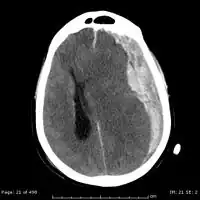

On a CT scan, subdural hematomas are classically crescent-shaped, with a concave surface away from the skull. However, they can have a convex appearance, especially in the early stages of bleeding. This may cause difficulty in distinguishing between subdural and epidural hemorrhages. A more reliable indicator of subdural hemorrhage is its involvement of a larger portion of the cerebral hemisphere. Subdural blood can also be seen as a layering density along the tentorium cerebelli. This can be a chronic, stable process, since the feeding system is low-pressure. In such cases, subtle signs of bleeding—such as effacement of sulci or medial displacement of the junction between gray matter and white matter—may be apparent.

Fresh subdural bleeding is hyperdense, but becomes more hypodense over time due to dissolution of cellular elements. After 3–14 days, the bleeding becomes isodense with brain tissue and may therefore be missed.[22] Subsequently, it will become more hypodense than brain tissue.